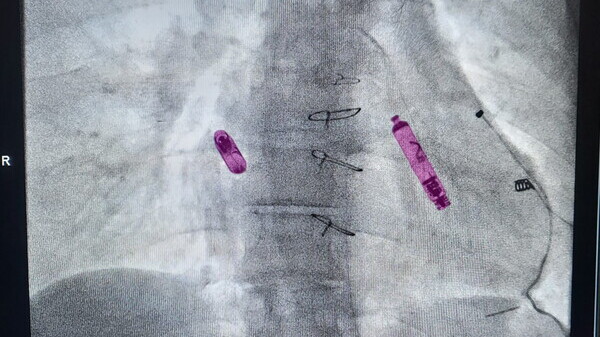

Nel caso specifico, l’équipe ha impiantato due dispositivi: uno nell’atrio destro e uno nel ventricolo destro. Questa soluzione consente una stimolazione “sequenziale”, cioè coordinata, tra atrio e ventricolo, favorendo una migliore tolleranza alle attività quotidiane. «Il pacemaker leadless è un micro-device totalmente intracardiaco che si applica sulla parete interna del cuore per garantire una stimolazione adeguata e coerente con l’attività del paziente – precisa il dottor Drago – È adatto solo per alcuni casi specifici, ma offre importanti vantaggi: nessun catetere, nessuna tasca chirurgica, maggiore comfort psicologico ed estetico, e un’efficienza paragonabile ai sistemi tradizionali».